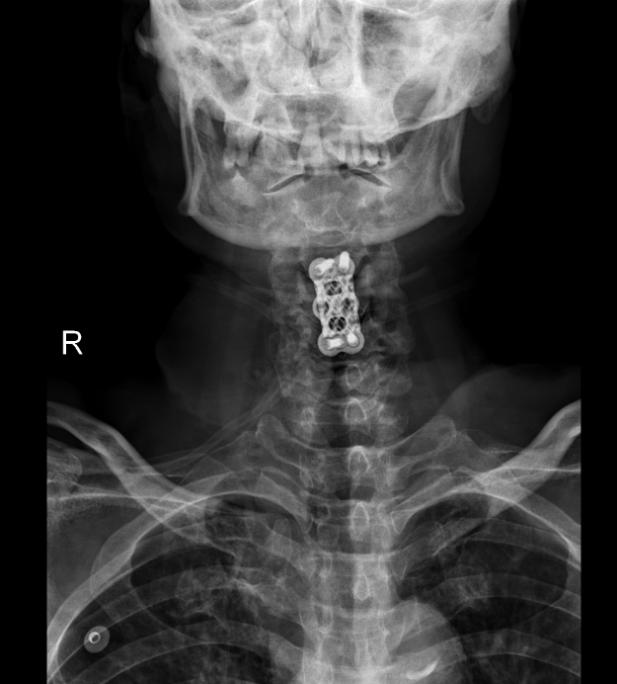

术后患者脊髓压迫解除,脊柱稳定性建立,在此基础上,专科化术后护理对巩固疗效、促进神经恢复、防范并发症同样至关重要。

4.5  患者术后影像